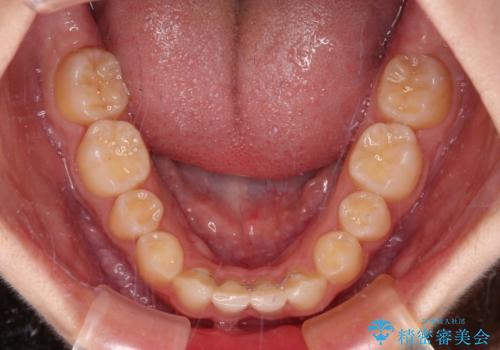

下顎の左右側切歯2本が欠損しており、上顎歯列がデコボコとなっている状態でした。

下顎歯列に対して上顎歯列が相対的に大きくなっているため、デコボコとなっているだけでなく、下顎前歯が見えなくなるくらいのディープバイトにもなっていました。